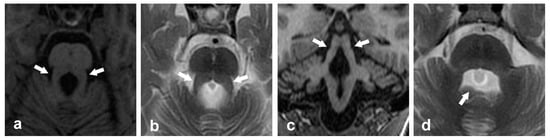

- Morphological features in the MCP: MCP width as well as midbrain and pons cross-sectional area has been shown to be reduced in patients with FXTAS compared to both premutation carriers without FXTAS and controls. Furthermore, decreased MCP width has been suggested as a potential biomarker to identify carriers at risk to develop FXTAS [8].

- Structural abnormalities in the SCP, MCP, and ICP and its correlation with molecular data: Significant reductions in FA and elevation of diffusivity have been described in the MCP and SCP of FMR1 premutation carriers with FXTAS [36,37,88]. The reported significant elevation of diffusivity measures in FMR1 premutation carriers without FXTAS [89,90] suggests preclinical change in white matter microarchitecture that warrants confirmation in longitudinal studies. Inverted U-shaped correlation between diffusivity measures and CGG repeat length was also demonstrated [36] as well as a negative dose effect of CGG repeat length and FMR1 mRNA on the connectivity strength of SCPs [37]. Negative correlation between the circulating FMR1 mRNA level and mean diffusivity in the MCP was also demonstrated in female premutation carriers without FXTAS. Additionally, decreased mean diffusivity in the MCP and ICP showed significant correlation with higher methylation levels in the FMR1 gene [40]. Currently, this is the only study that revealed FMR1 molecular correlation in the ICP.

- Metabolic abnormalities in the MCP: Significant decreased levels of metabolites NAA/Cr and Ch/Cr in the MCP of FMR1 premutation carriers have been described, plausibly representing axonal loss and demyelination [35].

- Clinical correlation: The MCP sign and microstructural white matter abnormalities observed in the SCP and MCP as determined by MRS and DTI studies have shown significant correlation with executive dysfunction, slow processing speed, dexterity, and cognition dysfunction in FMR1 premutation carriers [35,37].